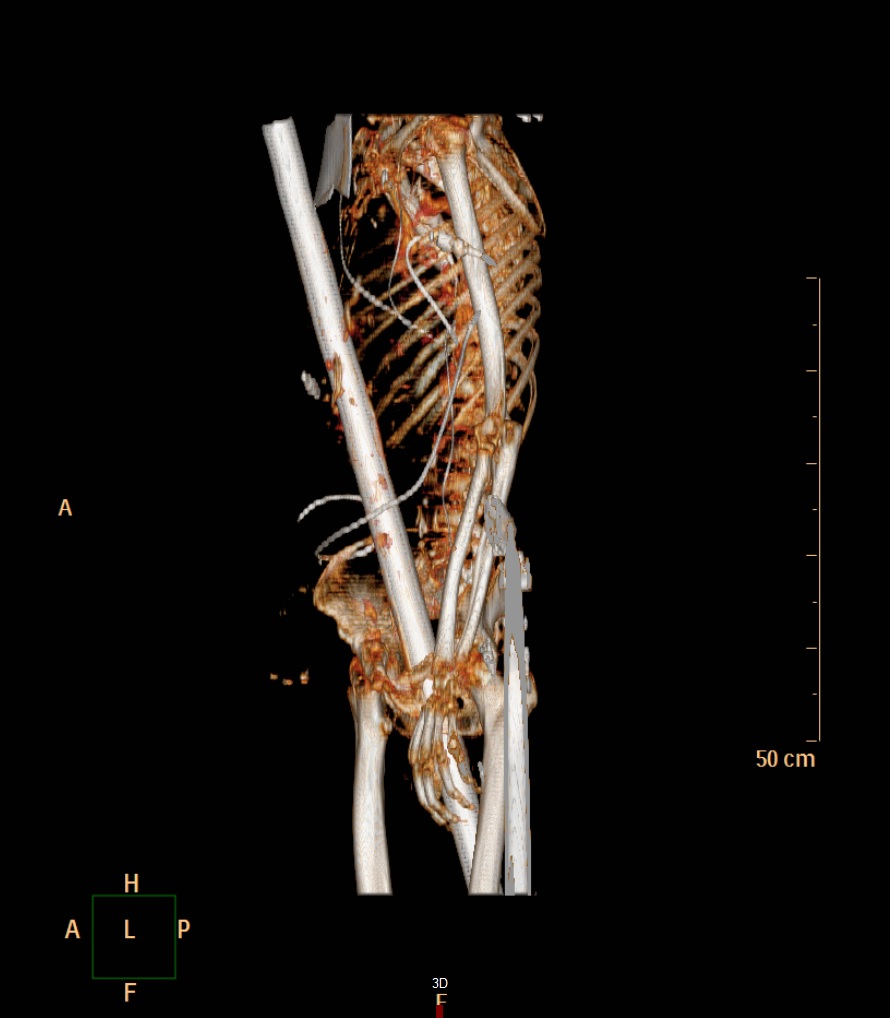

Frank Vaorin hatte unfassbares Glück im Unglück. Der 55-jährige Familienvater aus Cuxhaven stürzte bei Baumschnittarbeiten in seinem Garten von der Leiter, fiel vier Meter in die Tiefe und wurde von einer rostigen, mehr als einen Meter langen Zaunstange praktisch längs auf-spießt. Die Stange bohrte sich neben seinem After durch den Bauch, vorbei am rechten Dick-darm, an lebenswichtigen Gefäßen und der Leber, durch das Zwerchfell in den Brustkorb. Sie verschonte ebenso die Lunge, durchstieß einige Rippen und kam unterhalb des Schlüsselbeins wieder zum Vorschein.

Mediziner sprechen bei dieser Art von Unfall von einer Pfählungsverletzung. Kaum vorstellbar, dass die stabile Zaunstange einmal längs den Körper von Frank Vaorin durchbohrte, ohne ihn dabei lebensgefährlich zu verletzen. Die Teams aus Allgemein- und Viszeralchirurgie sowie Thoraxchirurgie befreiten Vaorin von der Stange.